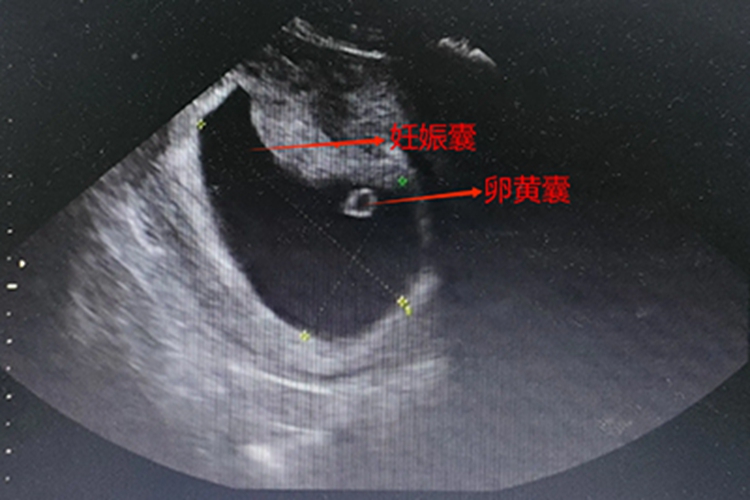

卵黄囊是孕囊内一个重要的结构,通常在怀孕5-6周时通过超声检查可以看到。在胚胎发育的早期阶段,受精卵着床后形成孕囊,随后在孕囊内逐渐出现卵黄囊。

- 卵黄囊的出现对于胚胎的正常发育具有重要意义,为胚胎提供营养、造血以及促进原始生殖细胞的发育。在怀孕早期,卵黄囊的存在和正常形态是判断孕囊发育良好的重要指标之一。